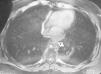

La exploración física fue normal. Los datos de laboratorio (hemograma, coagulación, perfil renal, hepático y nutricional y hormonas tiroideas) estaban asimismo dentro de la normalidad. La endoscopia digestiva alta mostró un mucosa orofaríngea muy eritematosa y con abundante moco. El esófago superior era normal y existía una dudosa imagen de compresión extrínseca en la cara anterior del tercio medio y distal del esófago, sin latido visible ni estasis alimentaria. El cardias era de aspecto laxo sin hernia de hiato y había una erosión de menos de 5 mm en el tercio distal del esófago. Una tomografía computarizada de cuello y tórax sólo demostró una hipertrofia amigdalar derecha. La resonancia magnética reveló una masa de 4,4 x 4,7 cm que parecía originarse en la unión esofagogástrica, con crecimiento hacia el mediastino posterior. La aurícula izquierda aparecía en posición anterior y los planos de separación con las estructuras vasculares estaban respetados (fig. 1). Ante estos hallazgos, se realizó una ultrasonografía endoscópica, que mostró en la unión gastroesofágica, por encima del diafragma y en posición anterior al esófago y el bronquio izquierdo, una formación bien delimitada de paredes regulares de 5 x 4,5 cm, con un contenido con brillo hiperecogénico y total ausencia de flujo tanto en su interior como en su pared. El tránsito esofágico mostró una impronta en la pared anterior del esófago distal por una formación quística mediastínica, sin comunicación con la luz, que no impedía el paso del contraste. Todos estos hallazgos nos plantearon el diagnóstico diferencial entre el quiste por duplicación esofágica y un quiste broncogénico, por lo que se planteó el tratamiento quirúrgico.

Fig. 1. Quiste de duplicación esofágico (flecha) en imagen de resonancia magnética.